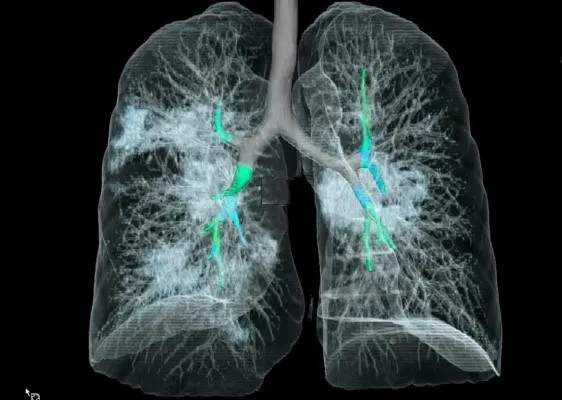

采用CT三维成像技术,

暴露在人们裸眼眼前,

到处是斑片状磨玻璃影(见下图)。

图片来自Radiology